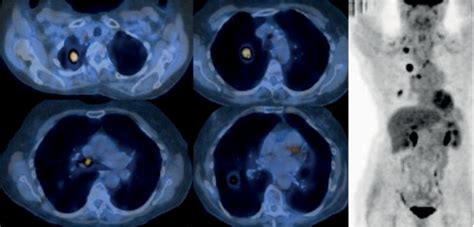

PET-CT scans are a powerful diagnostic tool that combines the strengths of both PET and CT scans. PET scans use a radioactive tracer to highlight areas of high metabolic activity, which is often indicative of cancer cells. CT scans, on the other hand, provide detailed anatomical images of the body. When combined, PET-CT scans offer a comprehensive view of both the structure and function of the body's tissues, making them invaluable in the diagnosis and staging of Pet Ct Lung Cancer.

PET-CT scans involve the injection of a radioactive tracer, typically a form of glucose, into the patient's bloodstream. Cancer cells, which have a higher metabolic rate, absorb more of the tracer than normal cells. The PET scanner then detects the radiation emitted by the tracer, creating images that highlight areas of high metabolic activity. Simultaneously, the CT scanner takes detailed images of the body's structures, which are then fused with the PET images to provide a precise location of the cancerous cells.

• Early Detection: PET-CT scans can detect cancer at an early stage, when it is more treatable. This early detection can significantly improve patient outcomes and survival rates.

• Accurate Staging: The detailed images provided by PET-CT scans help in accurately staging the cancer, which is crucial for determining the appropriate treatment plan. Staging involves assessing the size and extent of the tumor, as well as whether it has spread to other parts of the body.

Interpreting the results of a PET-CT scan involves a detailed analysis by a radiologist. The images are reviewed to identify areas of high metabolic activity, which may indicate the presence of cancer. The results are then shared with the patient's healthcare team, who will discuss the findings and develop a treatment plan. It is important to note that while PET-CT scans are highly accurate, they are not foolproof. False positives and false negatives can occur, and additional tests may be needed to confirm the diagnosis.